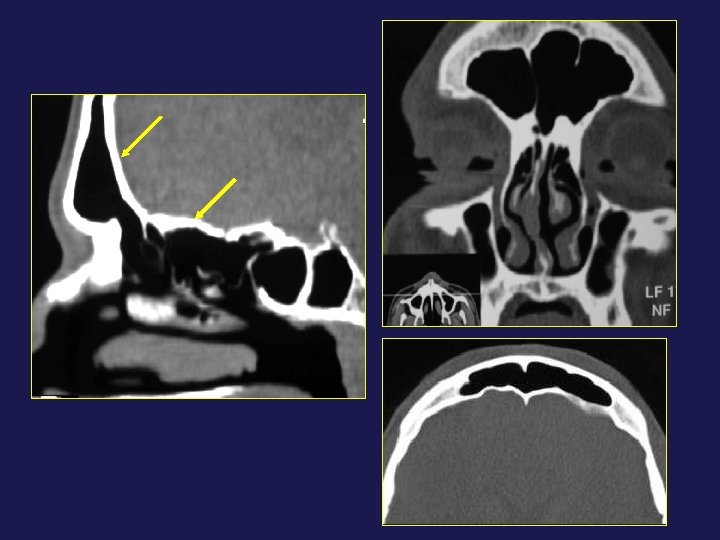

→ Fuite de LCR : brèche osseuse

→ Fuite de LCR : déhiscence osseuse